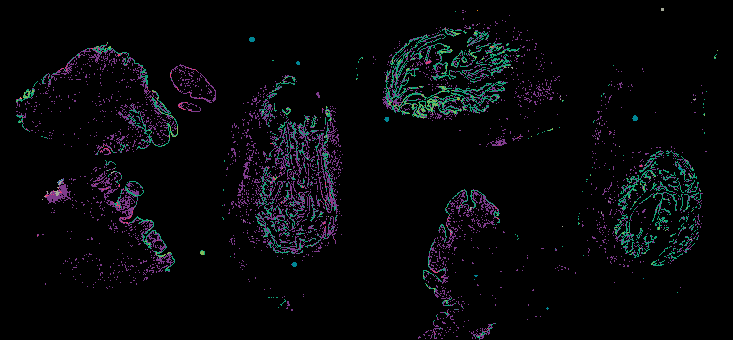

Curated stories provide access to images that have undergone a quality control step to remove failed markers, ensure appropriate channel intensity settings, and provide metadata about the underlying sample and image. Click the Minerva story icon for an interactive view of the full-resolution images.